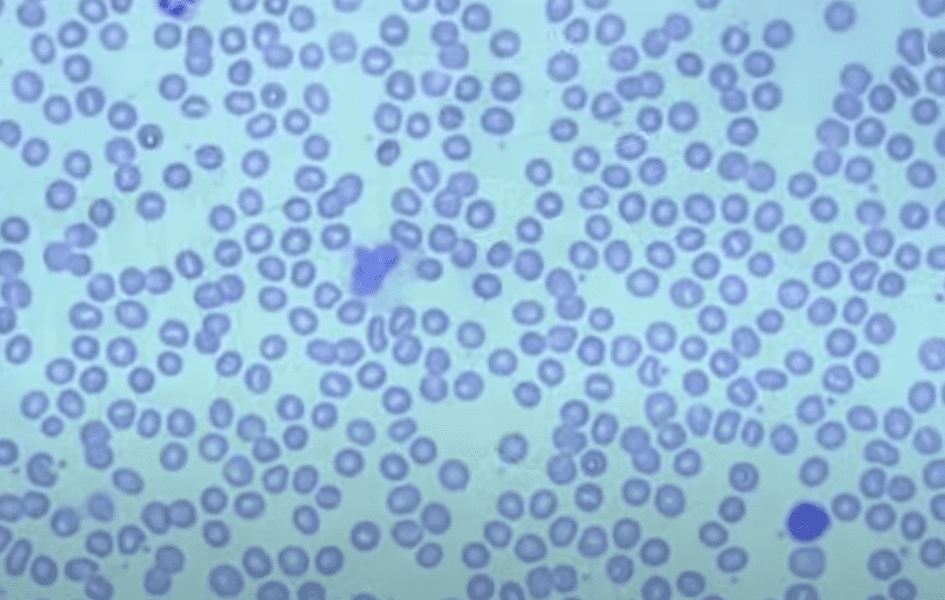

6. Red Blood Cells

Despite being called red blood cells, they appear blue under this microscope. Did you know there are around five million blood cells in every drop of blood? You learn something new every day.